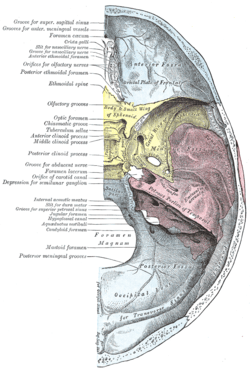

Base of the skull. Upper surface

Base of the skull. Upper surface Base of the skull. Inferior surface, attachment of muscles marked in red